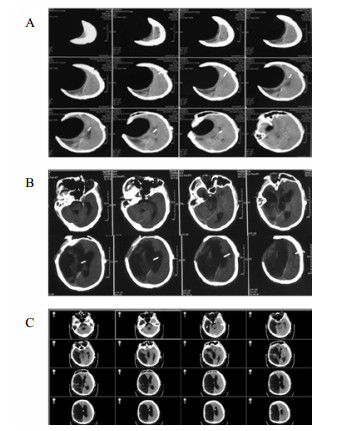

1 资料与方法病例1, 女,24岁,2015年12月以“脑干出血破入脑室术后1年,脑积水V-P分流术后”入院。入院时为植物状态,GCS 8分,双瞳孔3.0 mm, 对光反应灵敏,双侧巴氏征阳性;V-P分流调压阀压力为1.0(Medtronic, Minnesota, USA),储液囊外接引流管,压力为外耳道连线上方10 cmH2O (1 cnH2O = 0.098 kPa)。诊断为:脑干出血术后、脑积水、永久性植物状态(图 1)。

| A:2014年12月2日CT;B: 2015年12月8日入院CT,分流压力为1.0 图 1 病例1 CT |

将分流管压力降为0.5后的第6天,该患者复查头颅CT和意识水平均无明显改变;后经分流储液囊穿刺脑脊液外引流,每日引流量150 mL,持续10 d,仍无明显改变。再将脑脊液外引流量增至300 mL/d,患者行为学稍有变化,开始出现刺激后头部转动、手部摸索活动,眼球能视觉追踪。复查头颅CT示脑室形态略缩小。因此,在此基础上再次手术将分流管由原来的抗虹吸可调压管更换为非抗虹吸可调压管,压力设为1.0。患者意识水平进一步改善,术后第4天复查CT示脑室较前缩小(图 2),其大小形态接近正常。随访一年,患者生活能自理,E-GOS 5分。

| 图 2 病例1更换分流管后第4天头颅CT |

病例2,女,60岁,2017年10月以“动脉瘤夹闭和脑内血肿清除术后6个月,意识进行性下降2个月余“入院。入院时植物状态;查体:GCS 8分,双瞳孔3.0 mm,对光反应灵敏,双侧病理征阴性。右侧额颞部颅骨缺损大。入院头颅CT示脑室扩大。诊断为:右前交通动脉瘤术后、脑积水、头皮下积液、右额颅骨缺损、持续性植物状态(图 3)。

| 右侧额颞部颅骨缺损7 cm×9 cm,双侧脑室和三脑室扩大 图 3 2017年10月12日病例2的CT |

入院后于2017年10月30日行“颅骨修补+V-P分流术”。术后将分流管压力逐步调至0.5。患者术后意识无明显改善,复查CT示脑室仍显著扩大。观察2周后病情同前,遂将储液囊外接引流,每日引流量约200 mL,持续3 d,未见行为学及影像学明显变化。加大引流至每日300 mL,持续3 d后,患者自主睁眼增多;引流量增至每天400 mL左右,患者能呼唤下睁眼和视觉追踪。而停止脑脊液外引流后,患者则退步到引流前水平。决定通过按压储液囊促进脑脊液引流(按压600次/d),持续10 d后,睁眼时间延长但仍无意识。考虑到患者意识水平和引流量明显相关,增加按压储液囊频率至1 500次/d,患者又能呼唤睁眼,但CT未见脑室明显缩小。随后增加按压至2 000次/d时,偶尔能出现遵嘱活动,复查CT示脑室结构较前稍有缩小,但脑室仍显扩张。动态观察患者的行为学变化和反复CT随访,逐步升至4 000次/d,患者可表达简短言语,但脑室仍略扩大。随后每月按压次数递增1 000次直至6 000次,复查CT示脑室结构明显缩小(图 4A);患者意识显著改善,能简短正确对答。2018年6月病情稳定后,逐渐减少到3 000次/d, 并复查头颅CT(图 4B)。患者意识完全恢复,交流言语思路清晰,搀扶能行走。

| A:2018年3月27日头颅CT,此时6 000次/d,脑室系统明显缩小;B:2018年9月15日头颅CT,3 000次/d 图 4 病例2头颅CT |

病例3,患者男,76岁,因“突发头痛昏迷,动脉瘤栓塞脑室引流术后半年余,脑积水分流术后3个月”入院。入院体查:GCS 7分,植物状态,双巴氏征阳性。V-P分流调压阀压力为1.0,脑积水虽已行分流术,但脑室仍明显扩大。拟诊:左前交通动脉瘤栓塞术后,脑积水V-P分流术后,持续性植物状态。脑室压力低于外耳道连线5 cm, 持续外引流脑脊液100~200 mL/d,同时去枕卧位,腹带加压包扎,适当增加补液量和扩脑血管改善脑微循环,力求增加颅内压和脑顺应性。脑室压力逐渐上升,然后调压至0.5,期间多次复查未见脑室大小明显缩小;但患者出现对威胁有眨眼反应,偶尔能对视觉对象定位,转为微小意识状态。发病4年后,即80周岁时,因为肺部感染而再次入院,控制肺部感染期间,考虑脑室仍扩大状态,予按压分流阀600次/d,患者意识显著上升,能主动要求饮食并表达喜好,能和家属互动做简单游戏。随访头颅CT见脑室较前有所缩小(图 5C)。

| A:第一次入院CT(脑出血栓塞和脑室外引流后);B:常规治疗后脑室扩大仍明显;C:2018年7月5日随访 图 5 病例3 CT |

病例4,男,26岁,因“车祸致颅脑损伤昏迷6个月”而入我院。急诊行开颅血肿清除术后1个月因脑积水而行V-P分流术。入院体检:GCS 7分,植物状态,四肢肌张力高,双巴氏征阳性。入院诊断为:重型颅脑损伤术后,脑积水V-P分流术后,持续性植物状态(图 6A)。考虑V-P分流过度引流,将分流调压阀调至最高的2.5水平,骨窗压力和头颅CT没有明显改变。遂将分流管皮下缝扎完全阻断,骨窗压力逐渐升高,术后复查CT(图 6B), 同时患者意识水平改善至微小意识状态。因脑积水加重再行V-P分流术,并择期予右额颞颅骨修补重建,随访头颅CT见图 6C。随后患者恢复至GCS 15分。

| A:男,26岁,颅脑损伤术后6个月入院时头颅CT;B:2015年1月4日分流管缝扎后CT;C:2017年3月8日V-P分流和颅骨修补术后 图 6 病例4 CT |